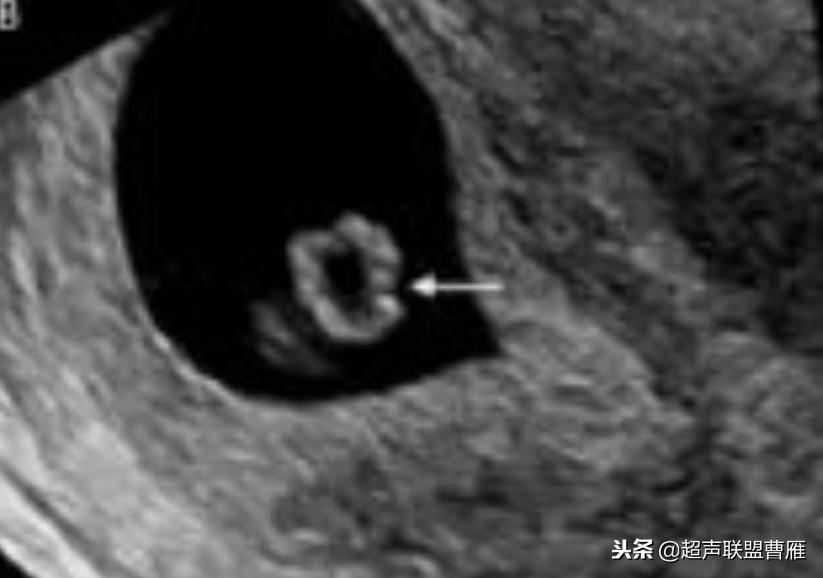

· 卵黄囊不规则或钙化:出现囊壁钙化或者增厚等形态改变以及囊壁缺损,提示 卵黄囊功能衰退与营养障碍,预示妊娠结局不良。一般情况下,出现钙化通常胚胎已停育。

钙化卵黄囊6.6mm,一周后胚胎死亡

卵黄囊回声增强,预后不良

卵黄囊钙化